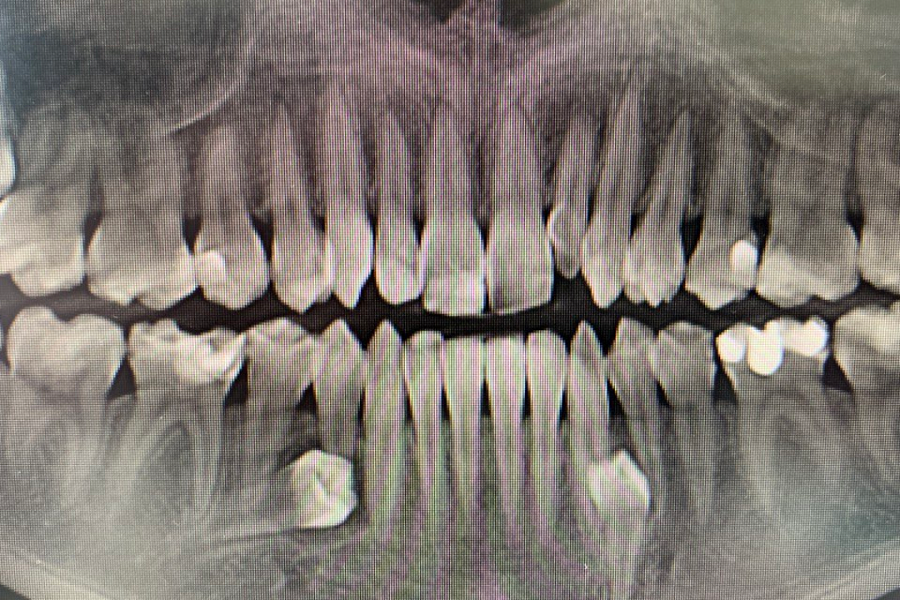

картинка

Зубы были удалены через окошко в кости, сделанное изнутри полости рта со стороны языка. Заживление прошло отлично, пациент ни на что не жалуется, соседние зубы не были повреждены.

На данный момент пациент продолжает ортодонтическое лечение.

Результат лечения